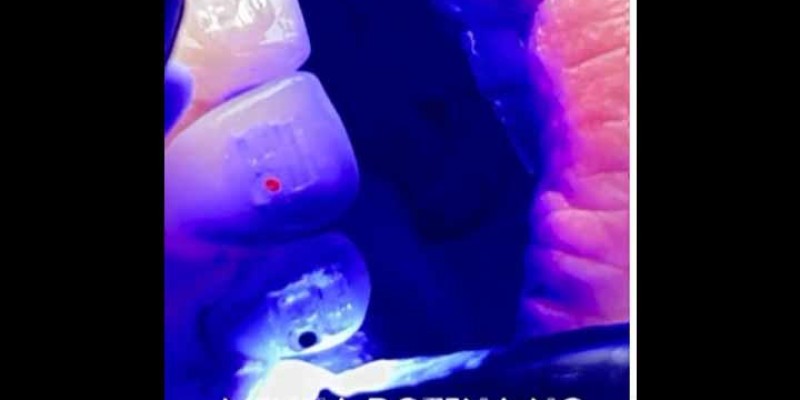

tratamento endodôntico; harmonização orafacial; fios de pdo; fio pdo; ácido hialurônico; aparelho ortodôntico;...

Tratamento Endodôntico, Harmonização Orafacial, Fios de PDO,...